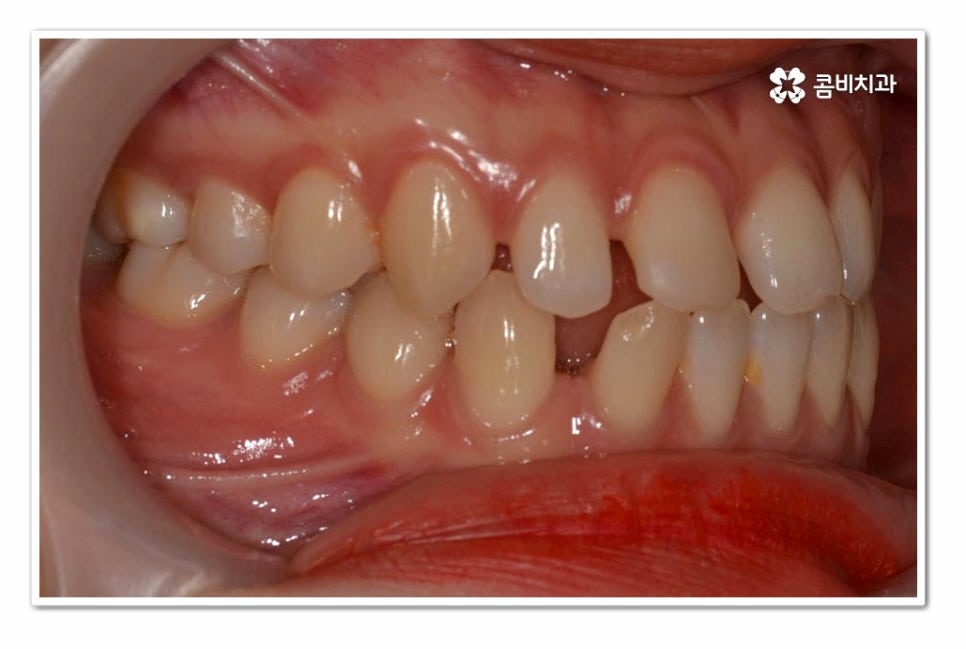

위 환자분의 경우 치아교정을 통해서 앞니 벌어짐 치료를 진행한 사례이며

치아의 이동 공간과 교합을 고려할 때 전체교정이 필요했던 사례라고 할 수 있어요.

위 환자분의 경우 윗니 만이 아니라 아랫니도 벌어져 있기 때문에

라미네이트와 같이 단기적으로 심미성을 고려한 치료보다는

치아교정을 통해 치아의 건강부터 교합, 심미성을 함께

개선할 수 있는 치료 계획을 세운 것이라 할 수 있어요.